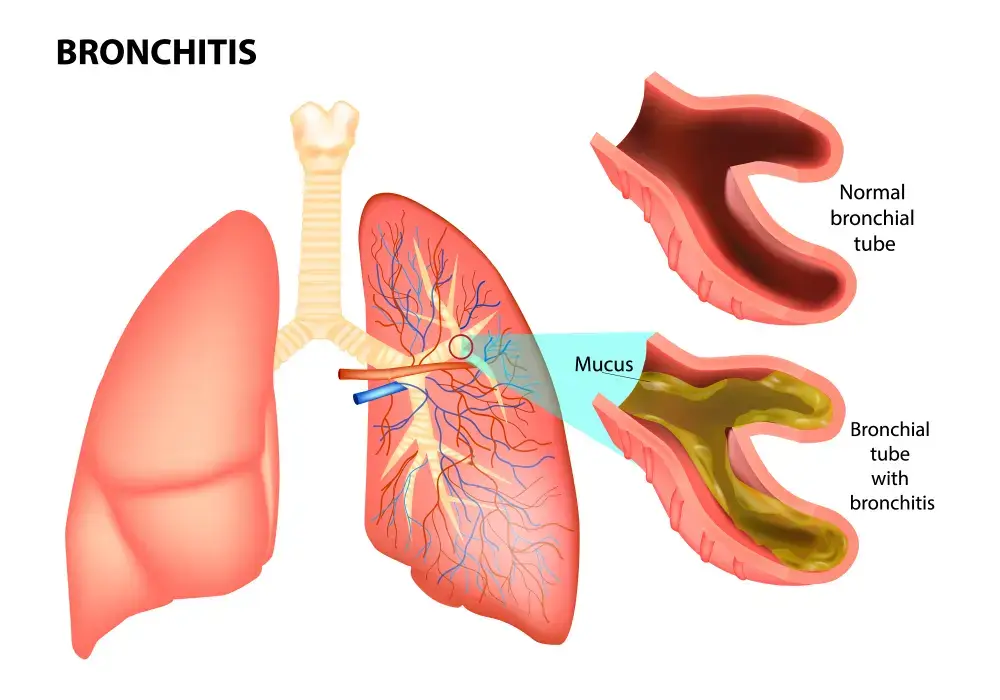

- Bronchitis • Georgetown • osteopathy • Natural Health Clinic of Halton (April 3, 2022)

- Respiratory System Conditions, Allergies, Asthma, Bronchitis • Georgetown • Naturopath • Natural Health Clinic of Halton (June 9, 2022)

- Infections – colds and flu, ear infections (otitis media, otitis externa), tonsillitis, bronchitis, sinusitis • Georgetown • Naturopath • Natural Health Clinic of Halton (March 19, 2017)

- Asthma, Bronchitis • Georgetown • Respiratory System • Natural Health Clinic of Halton (March 19, 2017)

- Bronchitis • Georgetown • Acupuncture • Natural Health Clinic of Halton (March 6, 2022)